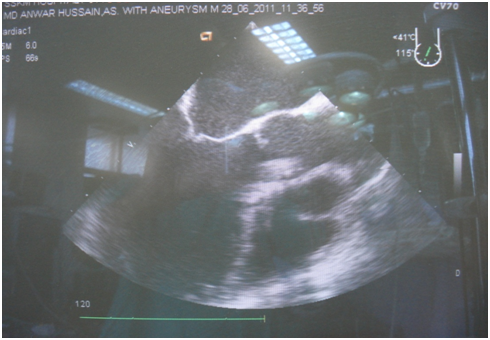

We presenting here a case of the patient with bicuspid aortic valve complicated with aneurysm of right sinus of valsalva. The aneurysm of sinus of valsalva was extracardiac and extending behind the main pulmonary artery and to the left. A 45years old Muslim male patient, carpenter by occupation was admitted with chief complaints of shortness of the breath and chest pain for 1 month. He was having orthopnoea and paroxysmal nocturnal dyspnoea and swelling of the feet. His vitals were stable with pulse rate 96/min, blood pressure 130/50mm Hg, and respiratory rate 14/min. On auscultation S1 was normal and S2 was soft with grade III/VI diastolic murmur in aortic area. Patient was properly investigated. ECG showed sinus rhythm and X-ray chest was showing cardiomegaly. Transthoracic echocardiography showed calcified bicuspid aortic valve, severe aortic regurgitation, grade II mitral regurgitation and that was appeared to be as dissecting flap in ascending aorta with 75% ejection fraction (Figure 1). Computed tomography chest was domne and it showed large pseudo-aneurysm of right sinus of Valsalva (Figures 2 & 3). Computed tomographic angiocardiography was done to define the lesion in the aorta accurately. Computed tomographic angiocardiography (Figures 4 & 5) revealed dysplastic aortic valve, para valvular aneurysmal sac communicating with aortic root as well as to left ventricle (? Pseudo-aneurysm). Routine investigations were done and patient was prepared for surgical intervention. Transoesophageal echocardiography was done in after induction of anaesthesia, which showed a large aneurysmal swelling behind the root of aorta. Conventional sternotomy was done. There were adhesions between pericardium and the heart. All adhesions were lysed. Aortotomy was done after institution of cardiopulmonary bypass. Bicuspid aortic valve and opening of the aneurysm were identified (Figure 6). Distorted, calcified aortic leaflets were excised and the opening of the aneurysm of sinus of valsalva was closed with Dacron patch from inside of the aorta (Figure 7). Aortic valve was replaced with sorin, bileaflet, mechanical valve, size 21 using interrupted ethibond, pladgeted sutures (Figure 8). Postoperative period was uneventful and patient was discharged on 7th postoperative day in good general condition. Patient is doing well in follow up visits.

Figure 1 Echocardiography.